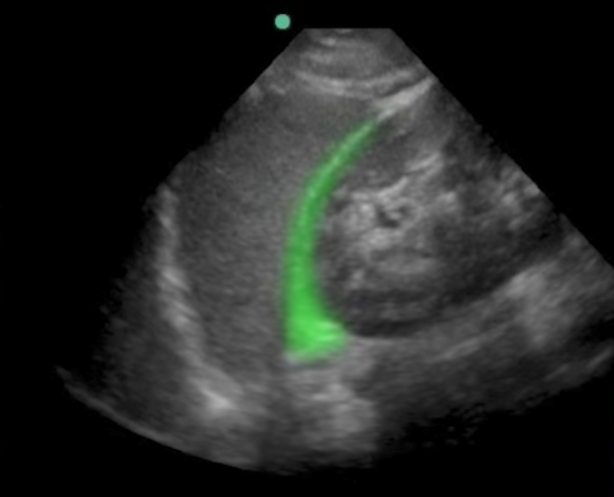

eFAST 左上腹 (LUQ) 图像

高亮区域:脾肾隐窝